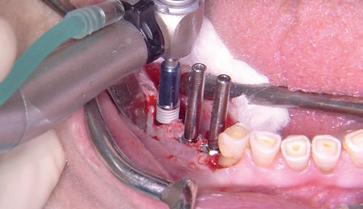

• Mise en pratique de la piezochirurgie.

• Réalisation des prélèvements de différents sites osseux et greffes : ramus, symphyse, pariétal pour mieux proposer ces solutions thérapeutiques.

• Réalisation de sinus lift, ostéosynthèse.

• Réalisation d’extractions atraumatiques : sauvegarde du capital osseux disponible.

• Réalisation de pose d’implants dans l’alvéole d’extraction.